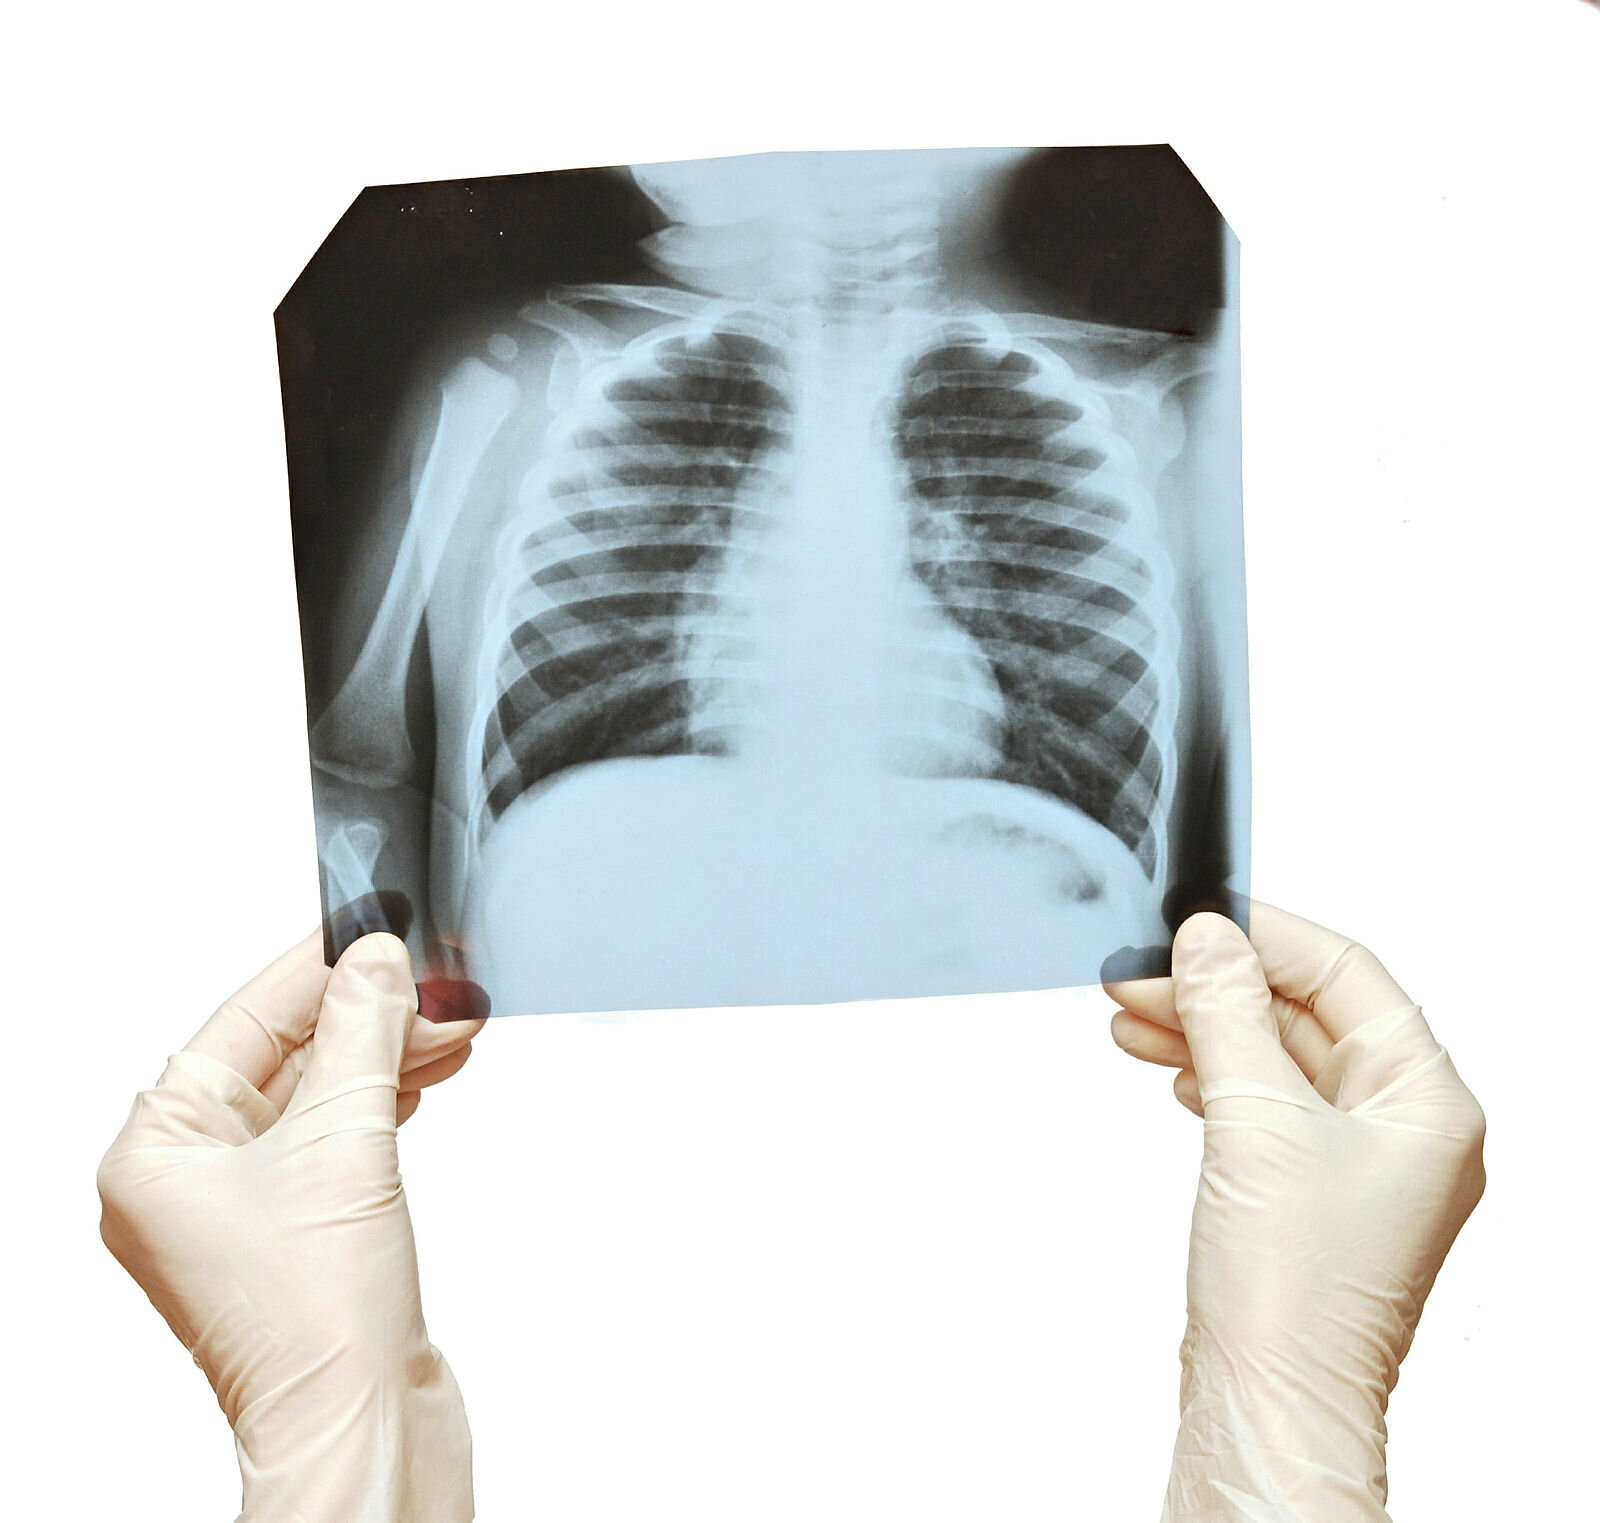

Kols er en sykdom som innebærer kronisk nedsatt lungefunksjon og skyldes først og fremst røyking, men også for eksempel støv i arbeidsmiljøet, ifølge overlege Per Nafstad ved avdeling for ikke-smittsomme sykdommer ved Folkehelseinstituttet.